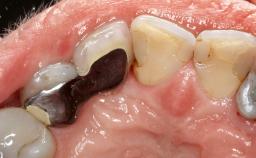

Treatment of Advanced Peri-Implantitis by Implant Removal Followed by Bone Reconstruction and New Implant Placement

Paolo Casentini and Matteo Chiapasco present a case in which the peri-implant defect was not suitable for a fully regenerative approach. It involves implant removal, use of a CAD/CAM customized titanium mesh in the grafting phase, and placement of new implants. A 62-year-old woman was referred for consultation regarding her implant-supported prosthesis replacing teeth 14 to 16. The patient’s main concern was pain and recurrent swelling in the right posterior maxilla. The patient also reported difficulty and discomfort when brushing the area. The patient reported she had been treated in another country, where she had received three implants in combination with sinus-floor augmentation for the replacement of the posterior maxillary teeth three years earlier. The patient indicated “endodontic complications” to be the reason for the extraction of the teeth.